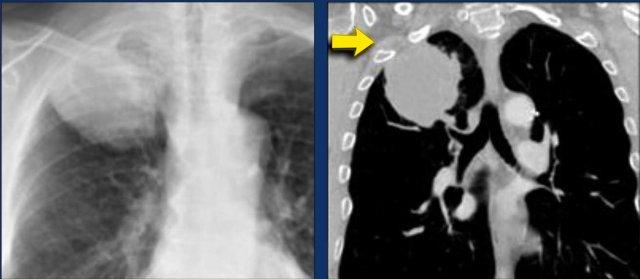

Hạch N3

Hạch N3 đại diện cho bệnh lý hạch trung thất hoặc rốn phổi đối bên, hoặc hạch cơ bậc thang hoặc hạch thượng đòn, và được xem là không thể phẫu thuật cắt bỏ.

Ví dụ:

Khối u bên phải với di căn hạch N3, bao gồm các trạm trung thất đối bên 4L và 5.

Các hình ảnh này thuộc về hai bệnh nhân khác nhau bị ung thư phổi ở phổi phải.

Hình ảnh

Có các hạch bạch huyết ở phía đối bên.

Nếu các hạch bạch huyết này chứa tế bào ung thư, điều đó có nghĩa là bệnh giai đoạn N3.

Hình ảnh của một bệnh nhân có khối u bên phải.

Có các hạch N3 ở phía đối bên và ở vùng thượng đòn phải.

Cuộn qua các hình ảnh để xem.